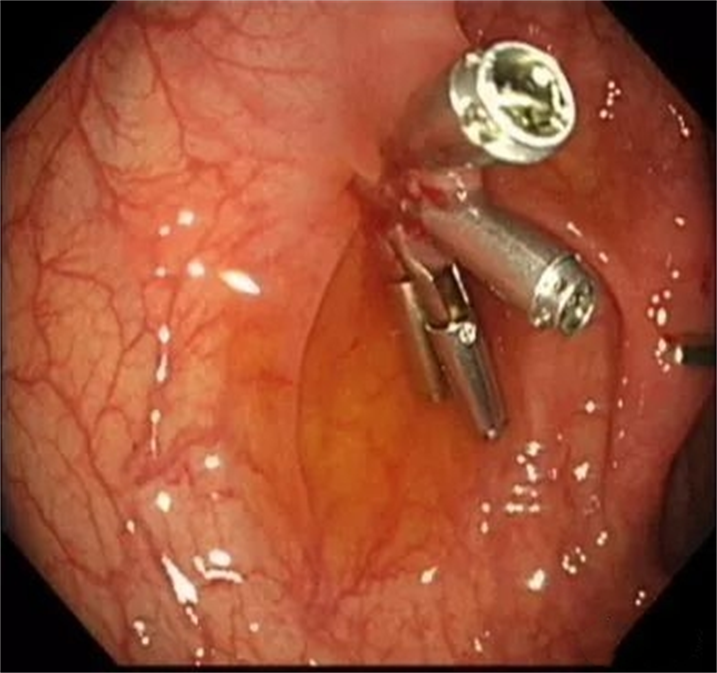

患者女性,42岁,无明显不适症状,例行肠镜检查,乙状结肠处发现一枚大小约1.0cm×1.5cm山田Ⅳ型息肉。

NBI仔细观察发现局部腺管排列紊乱,考虑局灶高级别病变。

粘膜下注射生理盐水,病灶抬举征明显,周围粘膜可见明显“白斑”。

然后,给予圈套器高频电切除病灶。

钛夹封闭创面。